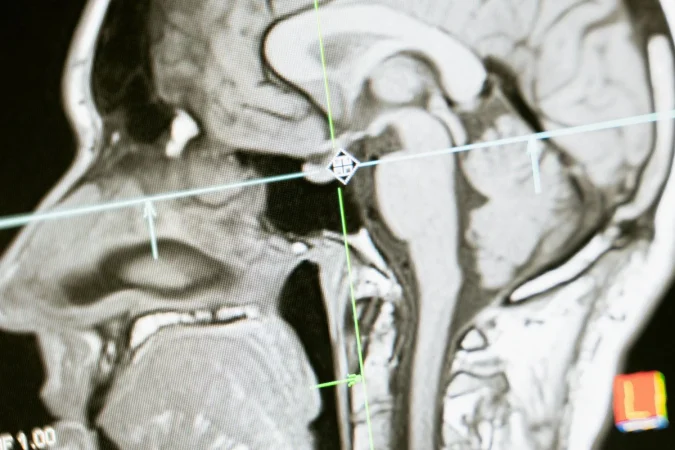

A los 10 años, Natasha Demakina, quien nació en Saransk, Rusia, notó algo inusual: podía ver dentro de los cuerpos de las personas. Ella afirmó que su percepción le permitió identificar dolencias internas como órganos, huesos y tumores, que solo son detectables con la tecnología médica moderna, como radiografías o resonancias magnéticas, de modo que siempre tuvo superpoderes.

La comunidad científica fue cautivada por este episodio y sometió a esta mujer a varias pruebas para determinar si realmente tenía poderes sobrenaturales o si era solo un truco, resultado de lo cual, llegaron a la conclusión de que los poderes de ojos de rayos X de esta mujer no podían ser explicados por la ciencia convencional, así que era necesario recurrir a explicaciones alternativas.